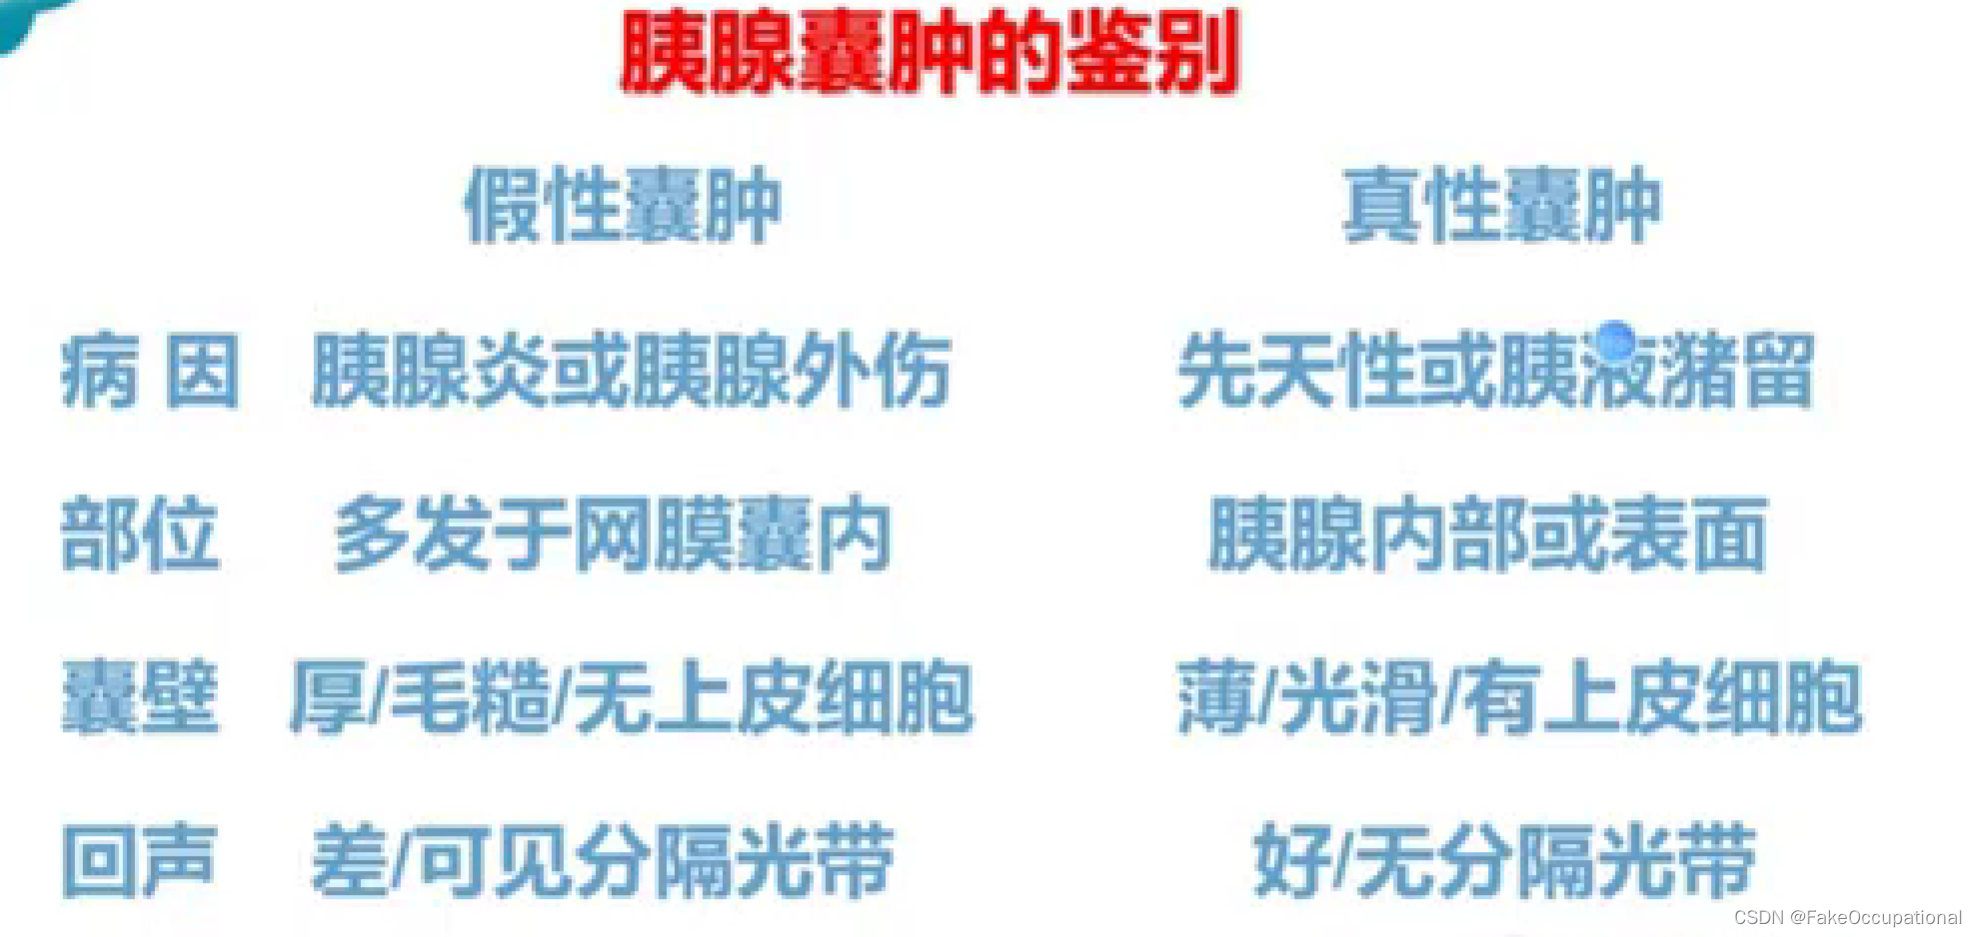

胰腺囊肿—假性囊肿、真性囊肿

胰腺真性囊肿

临床: 胰腺本身形成的囊肿,囊液由囊壁的上皮细胞分泌而来,多数没有临床症状,囊壁比较薄,内透声好.

分类:先天性囊肿

猪留性囊肿

寄生虫性囊肿